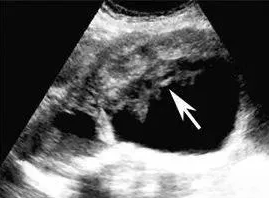

图4,胆囊癌。

超声检查能清晰的显示肝胆系统,直接显示胆囊壁的增厚和胆囊腔内的肿块以及肝脏和淋巴结的转移灶。被临床公认为诊断胆囊癌的首选检查方法。

胆囊癌的声像图可分为5型:小结节型、蕈伞型、厚壁型、混合型和实块型,其中厚壁型胆囊癌的囊壁呈现不均匀增厚,可以是局限型或是弥漫型,后者往往以颈部、体部增厚显著,内壁线多不规则。需与慢性胆囊炎所致的囊壁增厚鉴别。

胆囊癌引起的胆囊壁增厚,需要尽早手术切除,然后根据病情判断是否需要化疗。